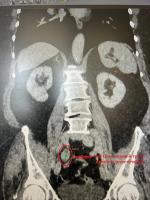

В урологическое отделение Коломенской больницы бригада скорой помощи доставила 63-летнюю женщину с кровотечением из мочевыводящих путей. Обследование показало, что причиной стала опухоль в мочеточнике.

Ситуация была осложнена наличием у пациентки крайней степени ожирения, а также хронической болезни почек 3 стадии. Стандартная в таких случаях операция по удалению почки и мочеточника привела бы к тяжелой почечной недостаточности и необходимости пожизненного гемодиализа.

«Мы приняли решение в пользу органосохраняющей и малотравматичной операции. Нашей главной задачей было не только удалить опухоль размером 4 на 2 см, но и сохранить функцию почки, избежав инвалидизации пациентки. Поэтому мы выполнили лапароскопическую резекцию пораженного участка мочеточника с последующей реконструкцией по методике Боари», – объяснил заведующий урологическим отделением Коломенской больницы, врач высшей квалификационной категории, доцент кафедры урологии Рязанского государственного медицинского университета им. акад. И.П. Павлова, кандидат медицинских наук Иван Собенников.